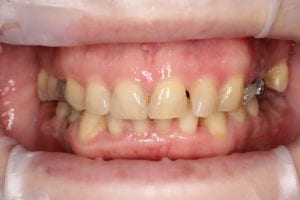

Пациентка 50 лет обратилась для замены старого съемного протеза верхней челюсти на новый несъемный (с просьбой об имплантации). После тщательной диагностики хирургом Борискиным А.А. и ортопедом Березиным А.И. была проведена одномоментная имплантация с нагрузкой временным несъемным протезом в первые дни после операции, что позволило пациентке почти не отвлекаться от работы, и получить несъемную конструкцию на верхней челюсти впервые за долгие годы. После достижения интеграции (не менее 6 месяцев) временные конструкции были заменены ортопедом на постоянные — цифровые из диоксида циркония с титановой балкой. Достигнута идеальная интеграция с мягкими тканями, эстетическая реабилитация и переход в желаемый цвет без затрагивания нижних передних зубов (пожелание пациентки).